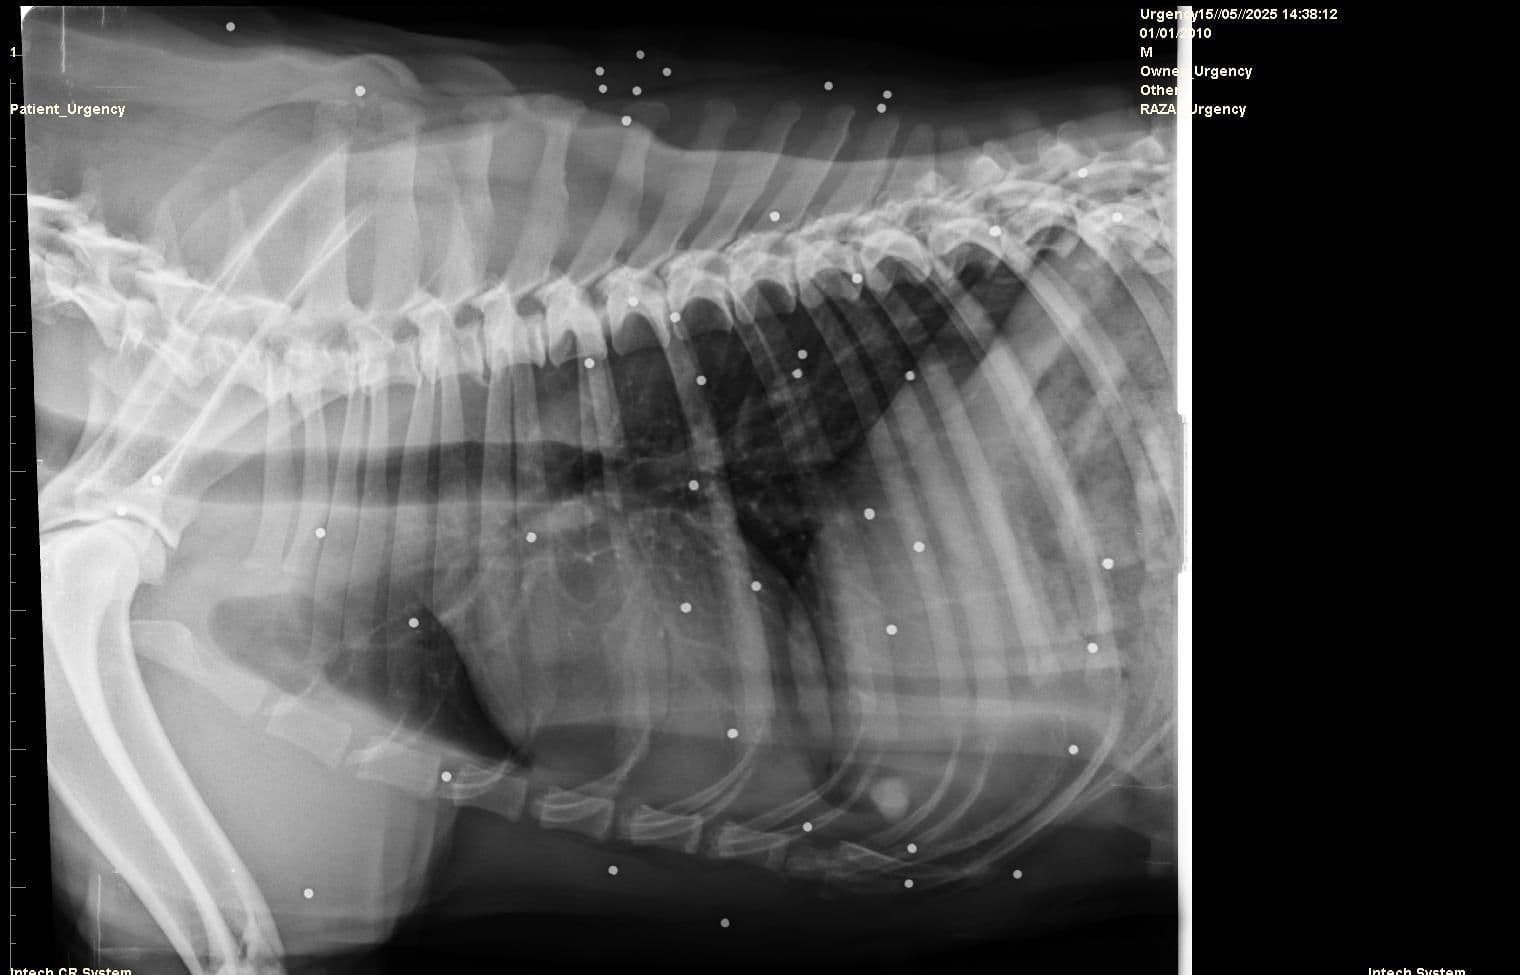

Bubba arrived at Los Barrios pound in May 2025 and was about 4 years old on arrival. She is a gorgeous cross breed that was found presumably abandoned in the streets and brought to the pound.BUBBA – SHOT, BEATEN AND BROKEN – BUT STILL STANDING 💔 Since arriving at the pound in May, Bubba has been slowly settling in. Little by little, she is beginning to enjoy gentle cuddles, and she now goes for walks on the quiet rural road near the pound. She walks well on the lead and doesn’t seem bothered by passing people or other dogs. Step by step, she is showing us that she wants to heal and that she hasn’t lost all hope in people.With new people, Bubba can be a little timid or wary at first. She may keep her distance until she feels safe — but offer her a treat, and she’ll soon come closer, curious and gentle. Once she knows you, she reveals her sweet, affectionate nature. She just needs a little time, understanding, and patience to show the loving dog she truly is.But her story began in pain. When Bubba first arrived, she had a visible wound on her head, likely from a strong blow. X-rays later revealed that her body was full of pellets. Someone had shot her — multiple times. How much suffering has this poor girl endured? How can anyone be capable of such cruelty?It’s no wonder Bubba kept her distance from people at first. She was wary, unsure, and hesitant to trust. And who could blame her? After everything she has been through, it’s a miracle she’s still alive — and even more of a miracle that she hasn’t given up on the world completely.Bubba is around four years old. We can only imagine what she has seen and survived in that time — perhaps it’s better that we never know. What matters now is that she is safe. She is with us, and we will do everything in our power to help her heal — slowly, gently, at her own pace.Bubba deserves kindness. Peace. And above all, a life free from pain. If you have experience with traumatised dogs and can offer a quiet, loving home, we would love to hear from you.